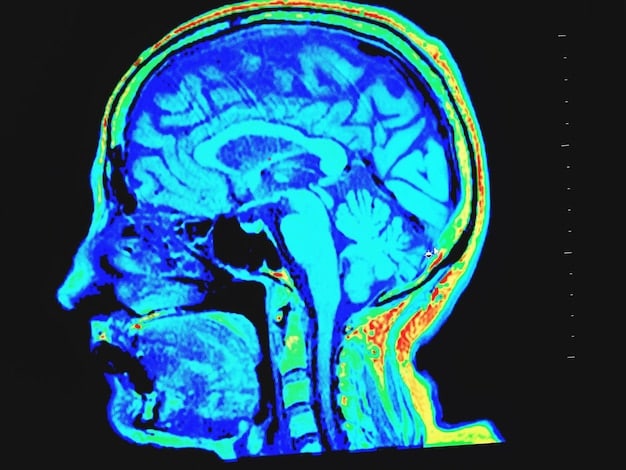

Brain Changes

Research has found that regular meditation can actually change the structure and function of the brain. For example, studies have shown that meditation can increase the gray matter in areas associated with attention, emotion regulation, and self-awareness.